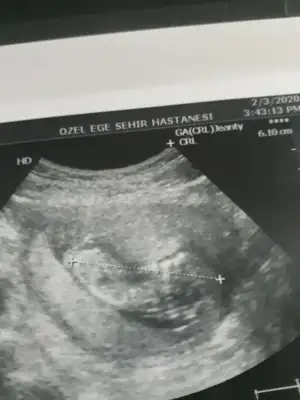

Buda benim bebişim 12 haftalık cinsiyeti sizce nedir😊

45CFB82A-2675-4DCE-89D8-BF5501063824.webp

Gecen 12 haftalik istemistiniz bugun cekildik yine :) tahminde bulunabilir misiniz